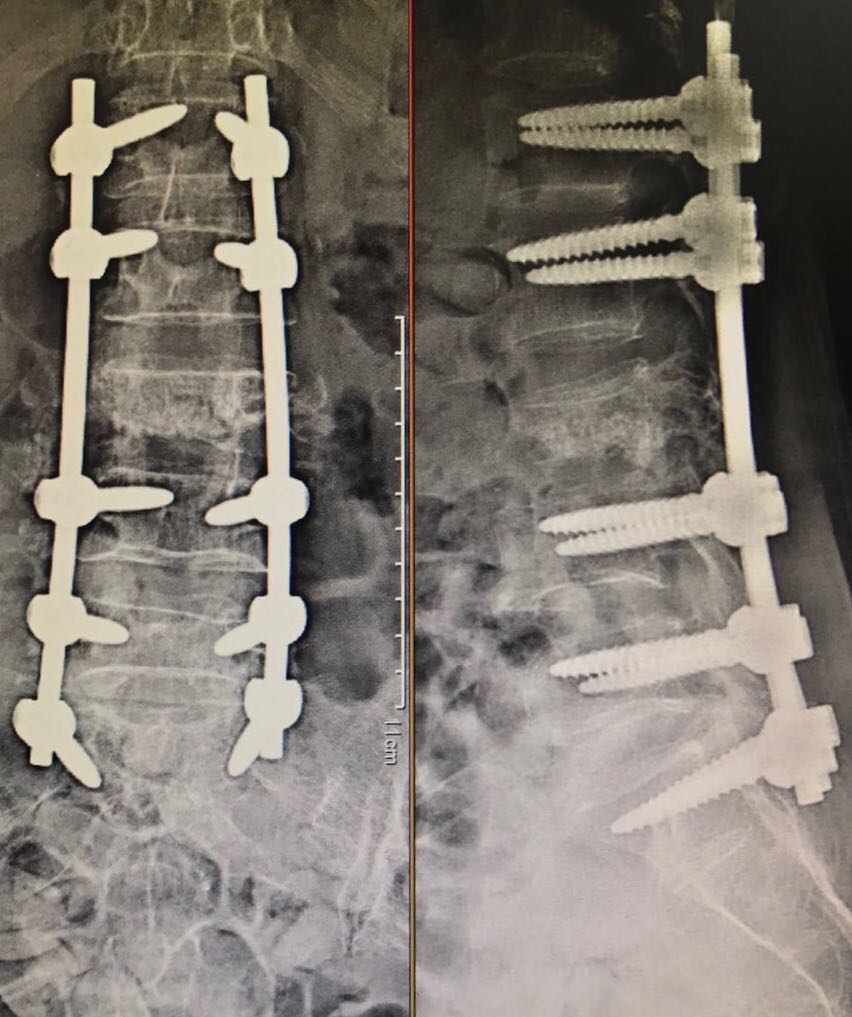

Neurosurgical procedures are often long and complex, requiring precise surgical skills along with concentration and stamina. This requires years of training. After completing his MBBS and MS degrees, Dr. Navneet Agarwal has 12 years of experience in neurosurgery. During this period, he performed brain and spine surgeries at the Neurosurgery Department of GR Medical College, Gwalior, the Trauma Center of SMS Medical College, Jaipur, and the Neurosurgery Department of Fortis-Escorts Hospital, Jaipur.

Now, Dr. Navneet Agarwal is an independent neurosurgery consultant. He has his own clinic near SMS Medical College in Jaipur. He performs surgeries for brain tumors, brain aneurysm clipping, coiling, flow diversion, brain strokes, and other spinal and neurological conditions.